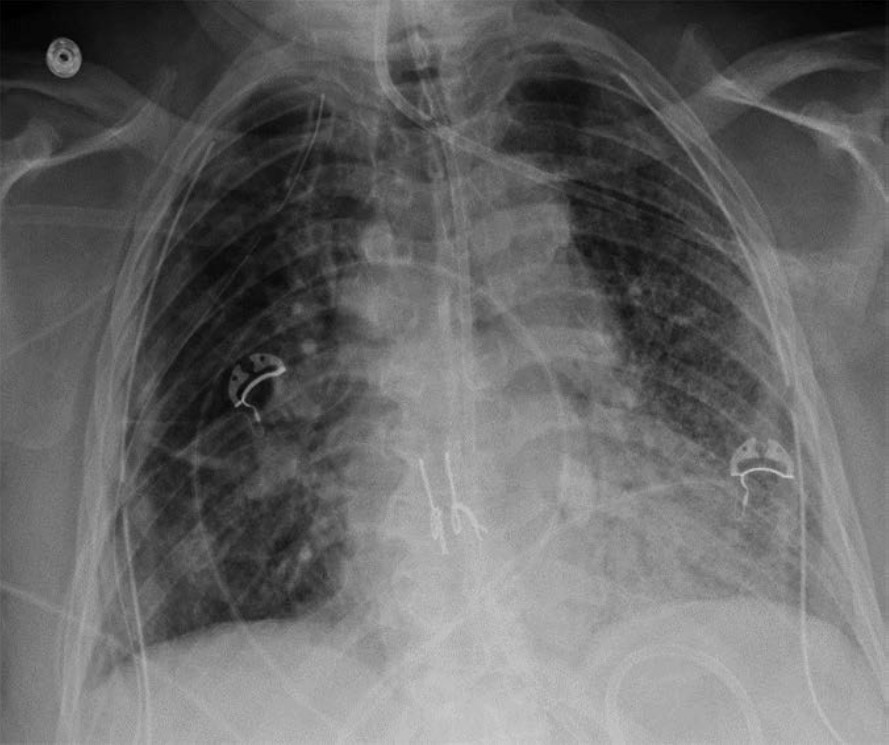

The clinical and imaging manifestations of pneumonia in transplant recipients are similar to those of nontransplant patients. Lung transplant recipients who present with dyspnea, cough, or fever are evaluated for pneumonia. Imaging findings of pneumonia include consolidation, ground-glass opacities, septal-line thickening, and pulmonary nodules. Pulmonary nodules can be single or multiple; they may be solid or ground-glass in attenuation. Cavitary nodules and nodules with ground-glass halos can occur, especially in patients with fungal pneumonia. Imaging studies should be scrutinized for complications of infection such as pulmonary abscess and bronchopleural fistula. Patients may also have reactive pleural effusions or reactive mediastinal or hilar lymphadenopathy. Treatment is the same as in nontransplant patients and consists of antibiotics, antivirals, or antifungals depending on the causative pathogen. Figure 4 shows three different lung transplant recipients with pneumonia.